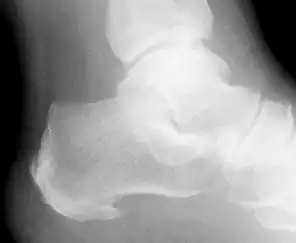

![]() Radiografía que muestra un espolón calcáneo inferior. | ||

El espolón calcáneo es un crecimiento óseo anómalo, que se desarrolla debajo del hueso calcáneo del pie. Esto comúnmente ocurre debido a una tensión prolongada sobre la fascia plantar, una banda gruesa de tejido conectivo que conecta el hueso calcáneo con los dedos del pie. Los espolones calcáneos se encuentran comúnmente en asociación con la fascitis plantar, una condición inflamatoria que afecta a la fascia plantar.[1]

Un diagnóstico preciso de los espolones calcáneos es vital para el tratamiento y manejo adecuado. Las técnicas de imagen, como la radiografía o la ecografía, son útiles en el diagnóstico y permiten diferenciarlo de otras posibles causas del dolor en el talón. [1]